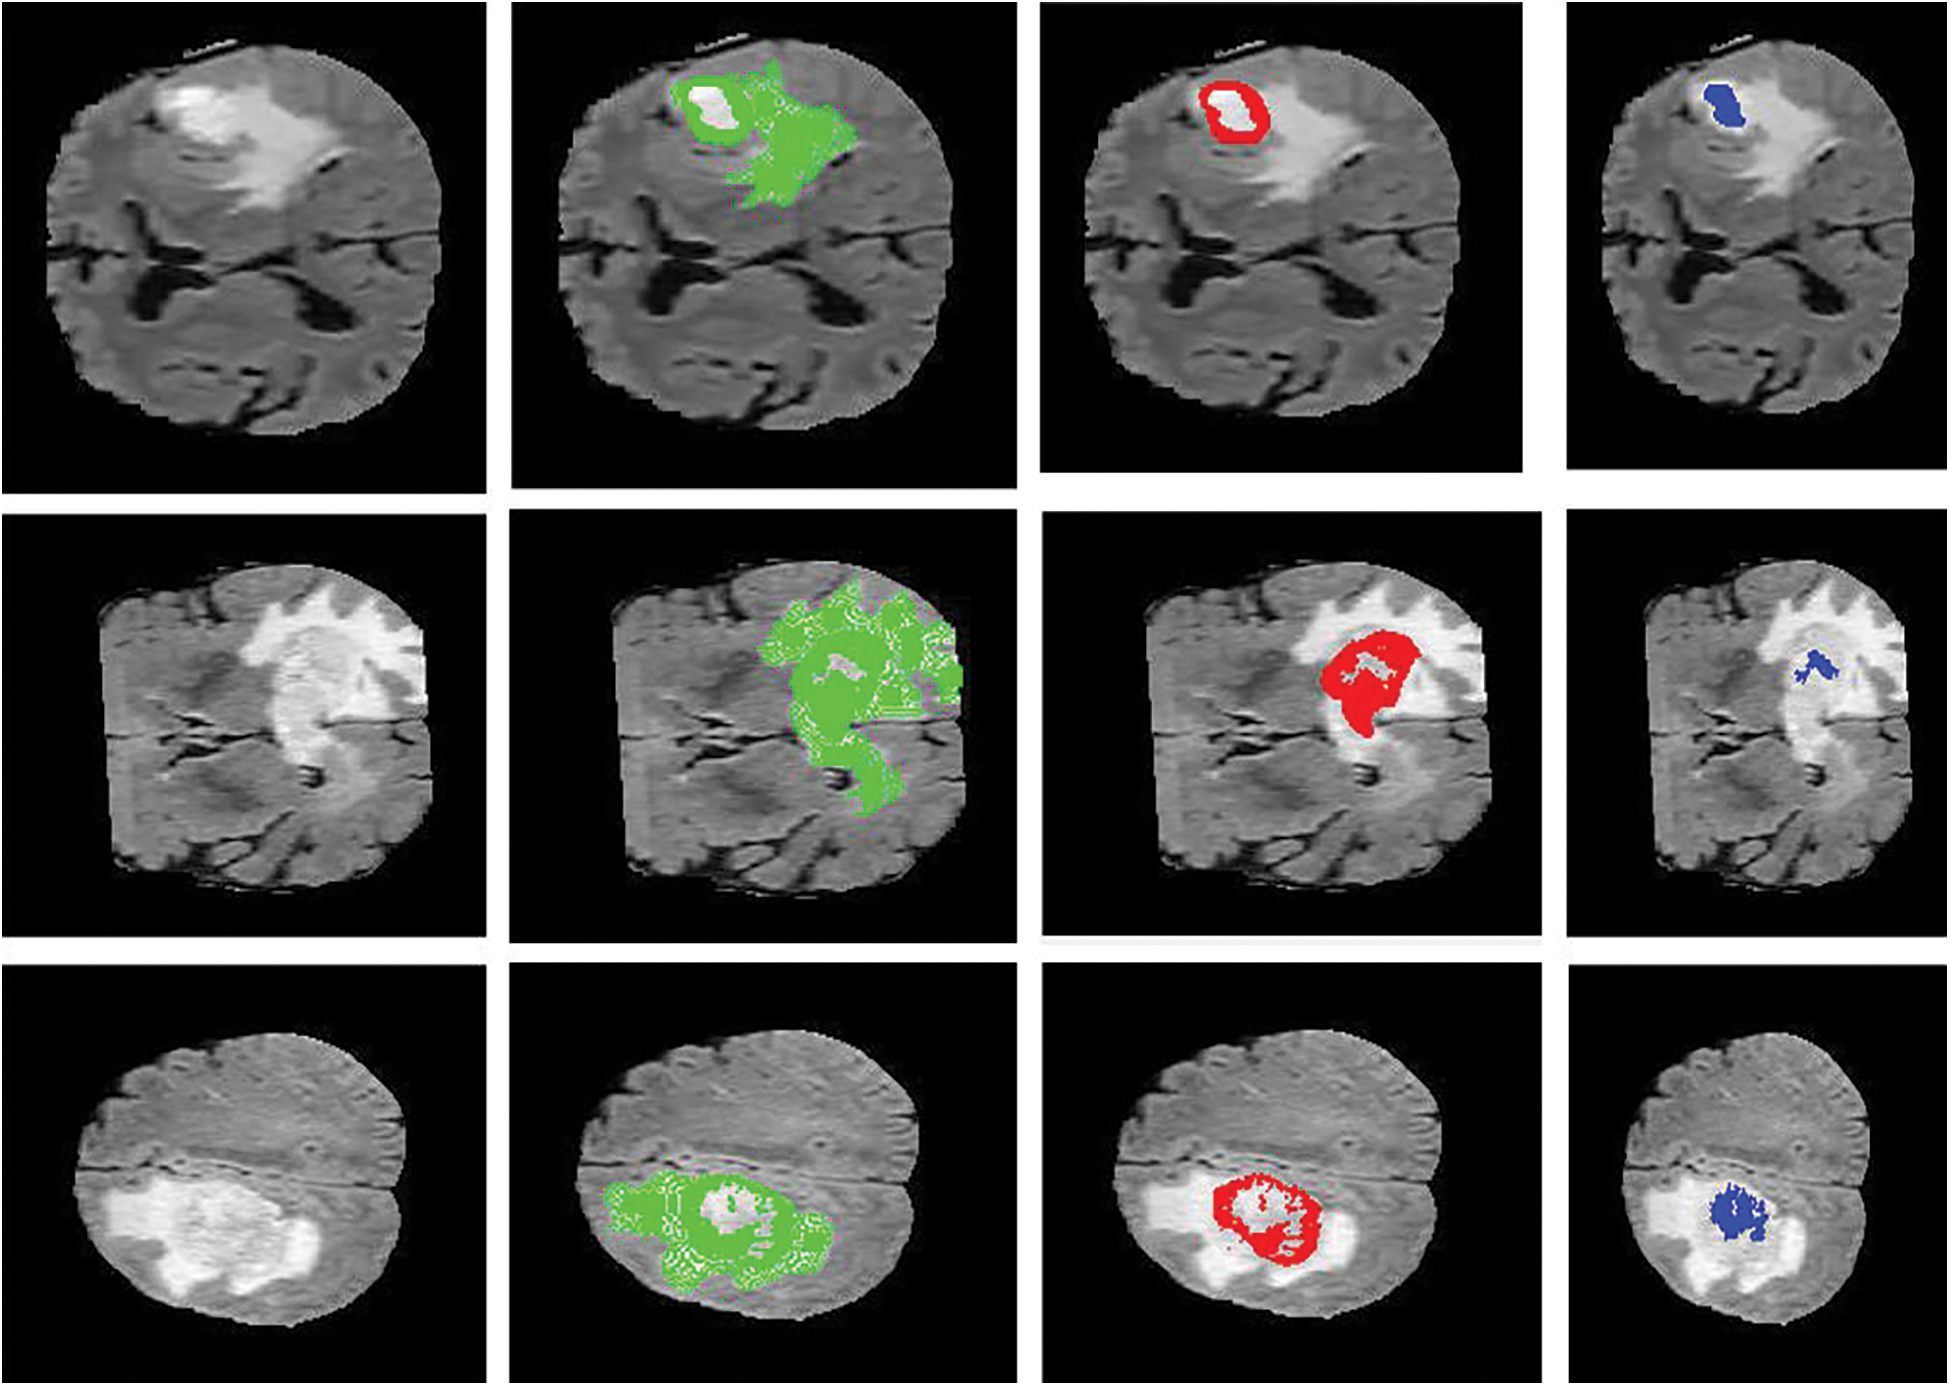

Figure 6: Sample visualization resutls (The first column shows the input image, second column represnets the Edema region, thrid column denotes the Enhancing region, and fourth column represets the Necrotic region)

The intratumor structures of edema, necrotic, enhancing tumor and nonenhancing tumor core have been clustered into regions of: The enhancing tumor region (ET) which contains entire tissues of tumor. (b) The tumor core region (TC) is used to enhance tumor, non-enhancing tumor core and necrotic. (c) The whole tumor region (WT). Sample visualization of the results attained are demonstrated in Figs. 6 and 7.

Figure 7: Sample visualization resutls (The first column shows the input image, second column represnets the Edema region, and thrid column denotes the Enhancing region)